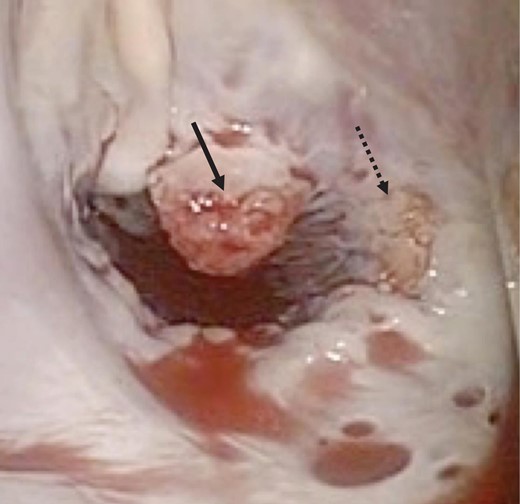

A 46-year-old woman with a history of long-standing SLE and APLS for >17 years and two recent cerebral infarctions was referred to our emergency department with a sudden-onset chest pain and dyspnea (New York Heart Association functional class III). Her usual steroid dose was 10 mg per day. Secondary to SLE associated thrombocytopenia she was anticoagulated with dabigatran. The EKG was consisted with anterior wall STEMI. Troponin level was 1.850. Coronary angiography showed obstruction at the distal left anterior descending and left circumflex arteries (Fig. 1). Transesophageal echocardiography demonstrated a preserved ejection fraction of the left ventricle and a mobile vegetation measuring 9 × 6 mm2 at the mitral valve (Fig. 2). Blood cultures were all negative. She urgently underwent mitral valve replacement through mini right thoracotomy to prevent further thromboembolic events. Cardiopulmonary bypass was undertaken femoral arterial and femoral and internal jugular venous cannulation. We did not perform coronary artery bypass graft because the obstructed arteries were quite distal. We identified a mass at the mitral A2 segment rough zone and two very small lesions at the A3 segment without annular calcification or submitral apparatus disease (Fig. 3). A2 segment was largely affected and shortened; therefore, we decided to not proceed the valve repair. Replacement was performed with a 27/29 mm On-X mechanical prosthesis (Medical Carbon Research Institute, LLC, Austin, TX, USA). Anterior and posterior chordae were spared. Aortic cross clamp time was 242 min and cardiopulmonary bypass time was 289 min. A pathological examination of excised valve leaflets demonstrated a fibrin thrombus without an evidence of microorganisms. The postoperative course was uneventful, and she was discharged 14 days after the surgery. She was followed up for 6 months, and her condition was stable.

Intraoperative photograph showing verrucous vegetations on the mitral valve of A2 (solid arrow) and A3 (dotted arrow).